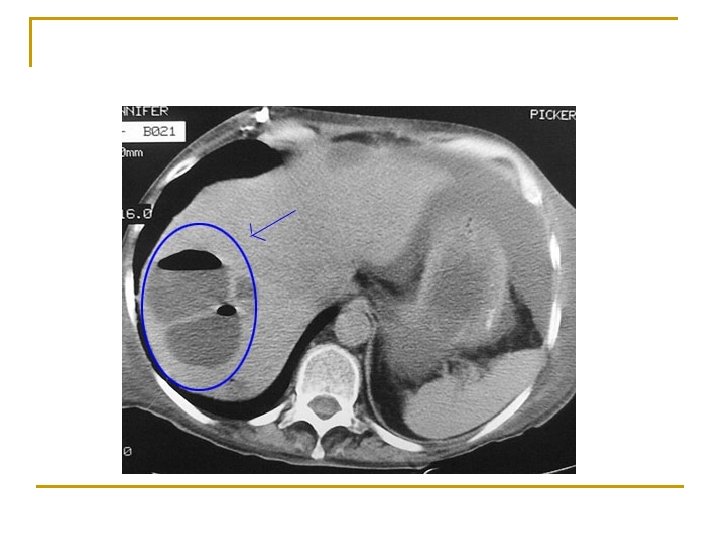

Karaciğer apseleri n n Genellikle piyojenik bakterilere bağlı gelişir. İnsidansı düşüktür (% 0. 013 -0. 035) Karaciğer apsesi soliter (%50) ya da multipl (biliyer kaynaklı) olabilir. Sağ, sol, kaudat lob

Tanı n n n Lökositoz (% 84 -88), ALP yüksekliği (% 60); diğer karaciğer fonksiyon testleri belirleyici değildir. Karın USG ve BT, kan kültürü (% 60 pozitif), apse kültürü. . . Multipl küçük apseler soliter apselerden daha mortal seyreder.